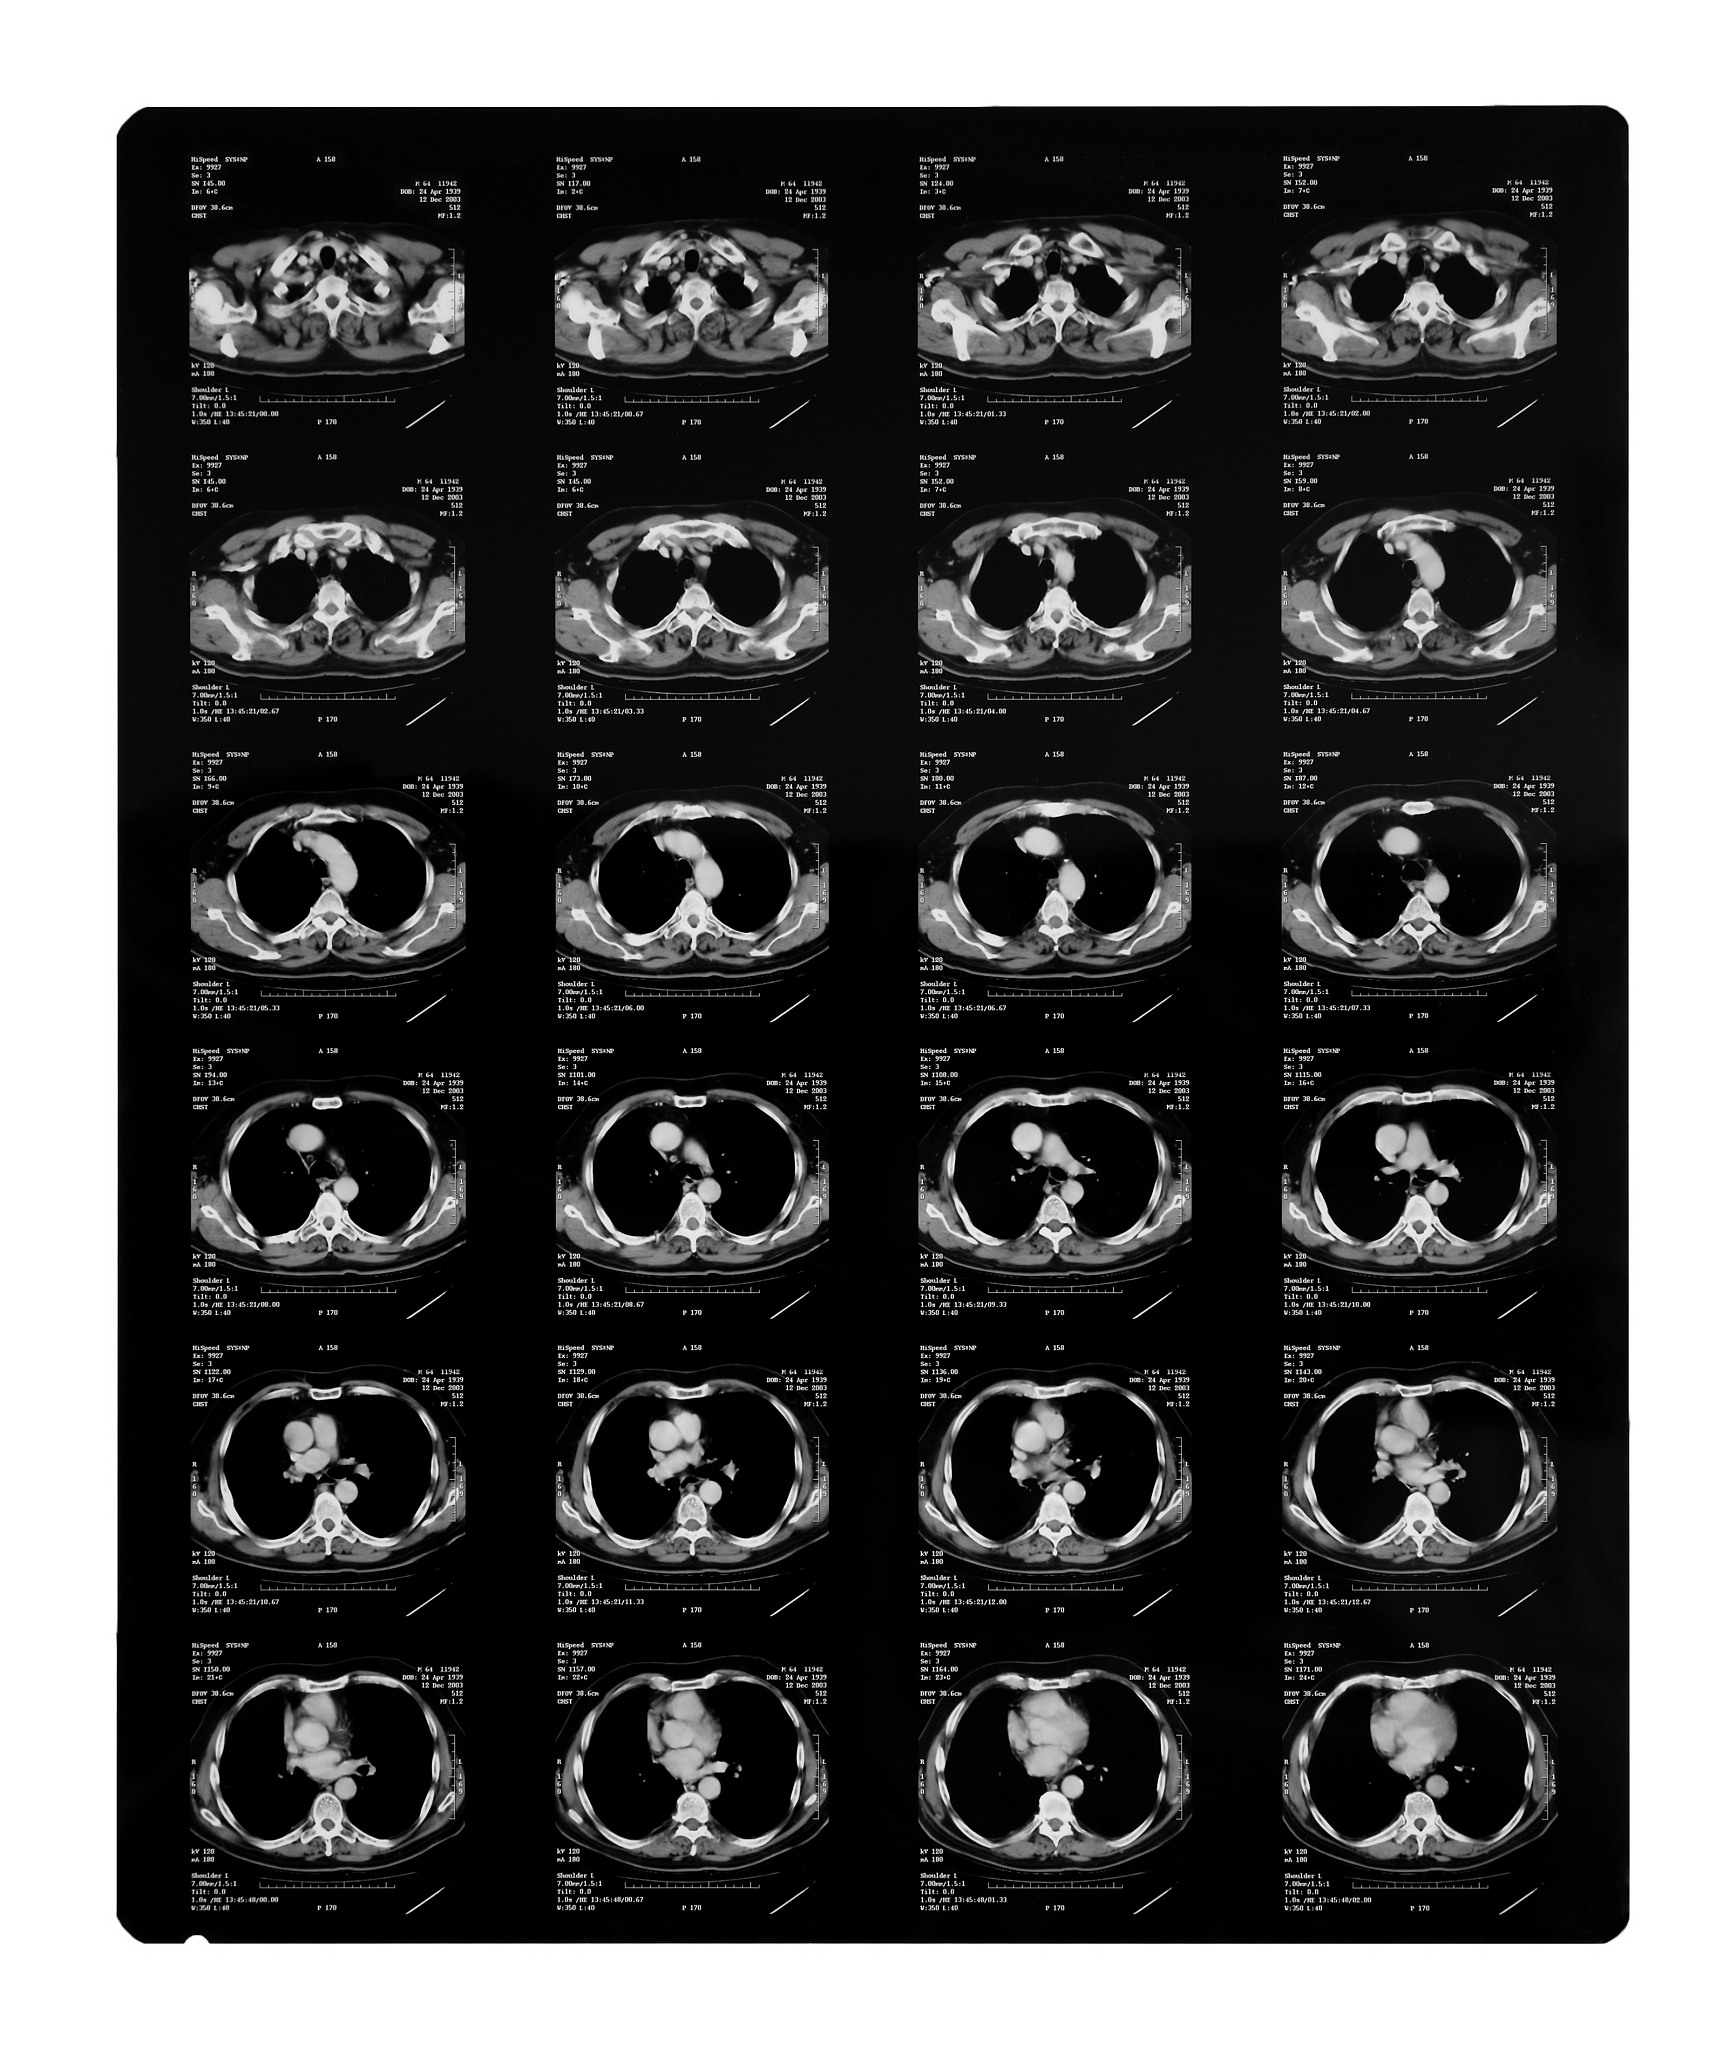

增强CT和增强MRI均能有效地评估颈动脉斑块内新生血管,以此来评估斑块稳定性。'Enhanced CT and enhanced MRI can both effectively evaluate neovascularization within carotid artery plaques, which can be used to assess plaque stability.'

颈动脉斑块新生血管评估:增强CT与增强MRI的有效性